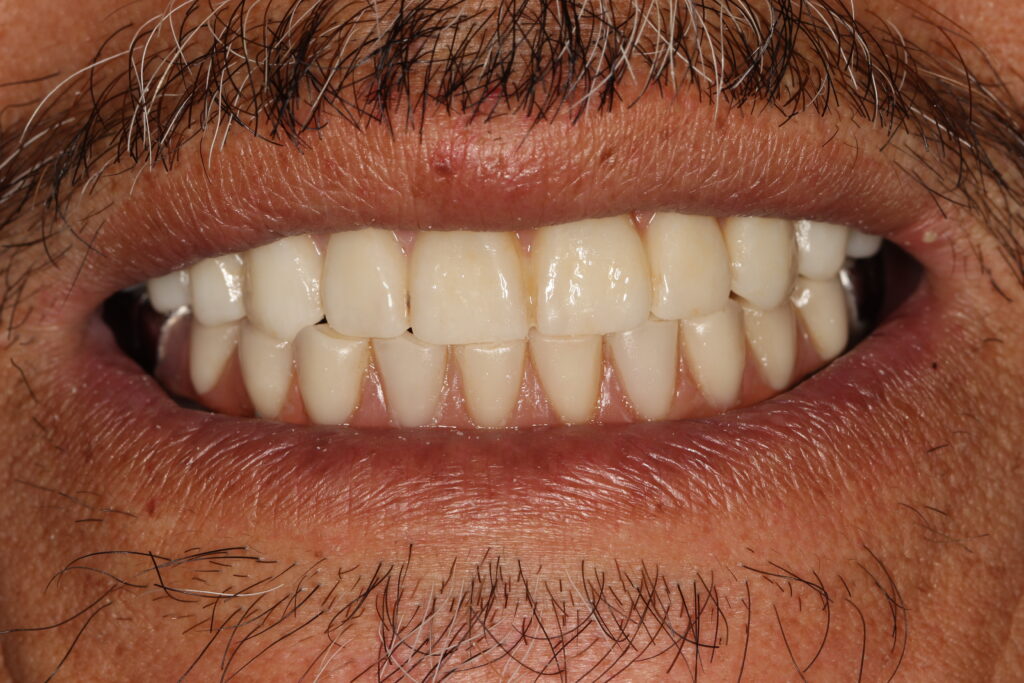

A selection of full arch fixed implant bridge patients after 5 years of wear

Oral Surgeons – Dr Han Choi, Dr Sam Goldsmith, Dr Rajiv Rajpal NSOMS

Prosthodontist – Dr Alan Payne NSOMS/Northland Prosthodontics

Dental technicians – Hosaka Takashi, DT Denture Design, Auckland, CJ Park, Project Dentistry, Auckland and Osteon Medical, Melbourne, Australia.